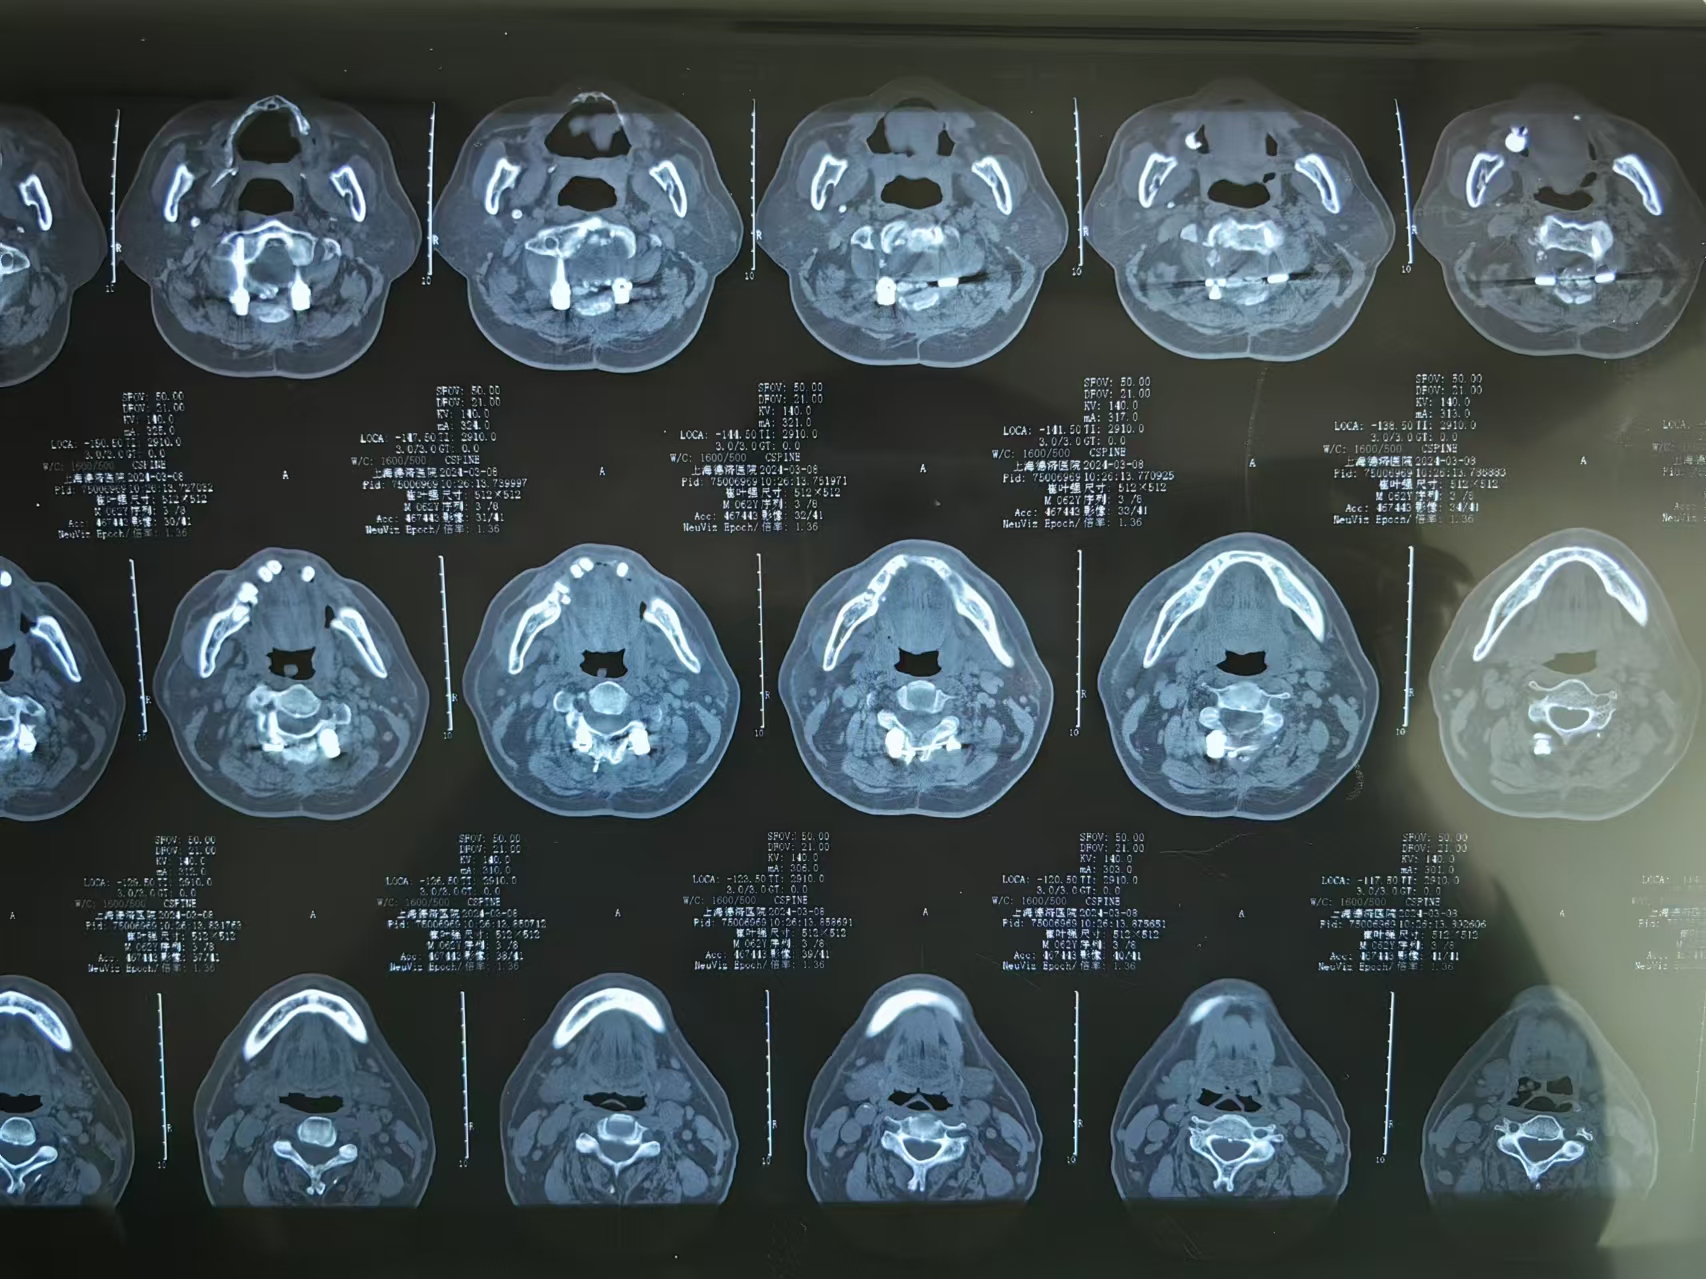

• 诊断:寰枢椎脱位,颅底凹陷

• 影像:

• 2023.09.01,复查,压迫脊髓。